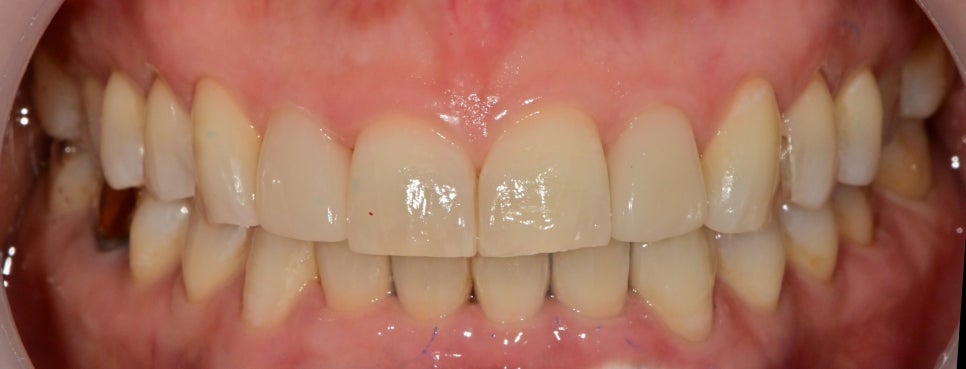

라미네이트 부착 후 원데이 미백직후의 사진입니다.

미백 후 라미네이트와 색상 차이가 날까

걱정하셨었는데 다행히 색상이 잘 나온 것 같습니다.

추후 한두 번의 미백을 하시면 훨씬 자연스러울것 같습니다.

기존 치아들이 각진 형태이기 때문에

라미네이트를 둥근 형태로 만들기에는 한계가 있어

닫힌 공간만 살짝 열어줘 개방감을 주려고 했습니다.